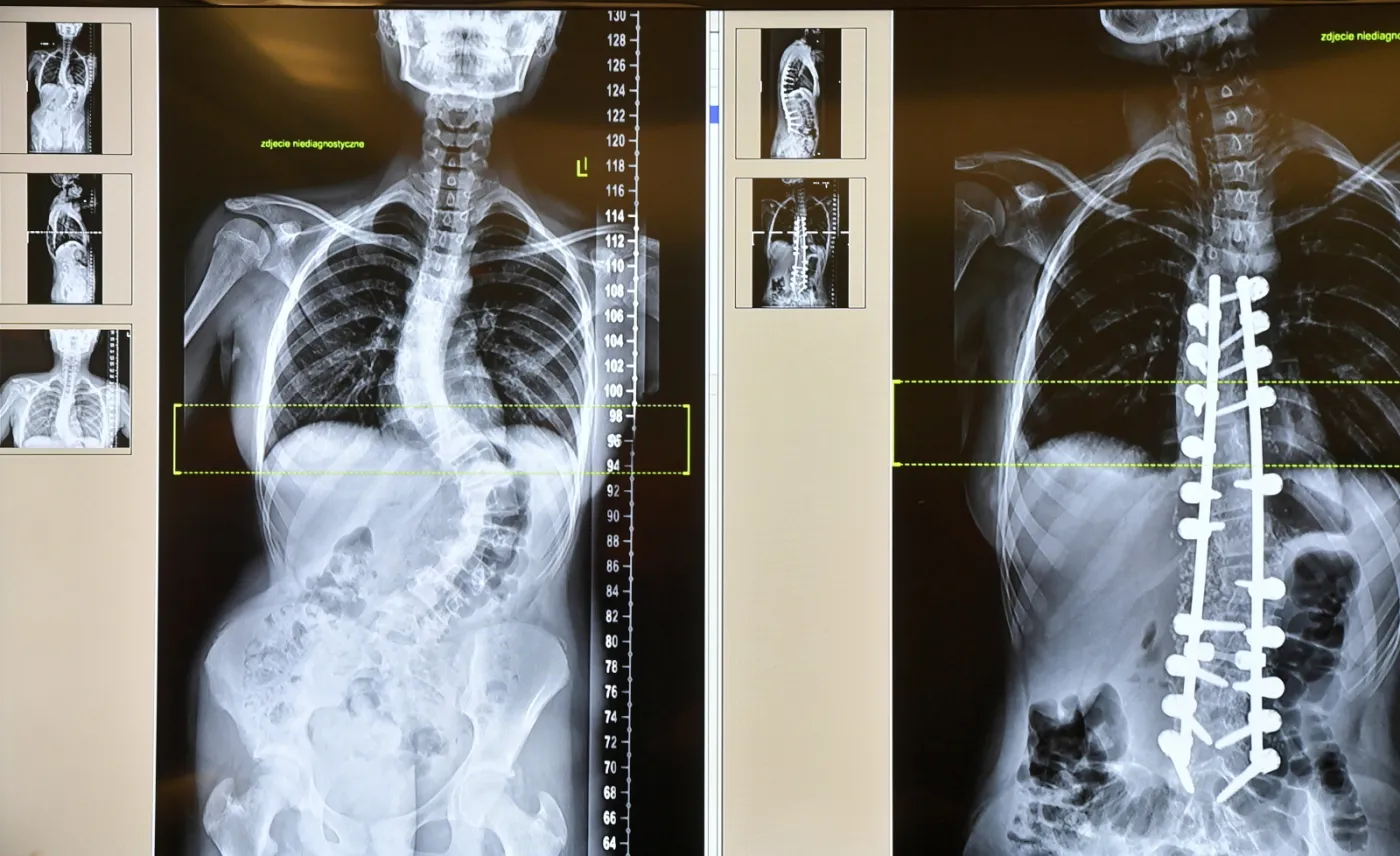

Operację korekcji zaawansowanej skoliozy u 13-latki przeprowadzili lekarze w szpitalu w szczecińskich Zdrojach. Podczas 50. takiego zabiegu w placówce zastosowano nowatorski system i pręty korekcyjne wykonane specjalnie dla młodej pacjentki. Wszystko po to, by ustawić wygięty o 85 proc. kręgosłup dziewczynki w prawidłowej pozycji i umożliwić jej powrót do normalnego życia.

Zdjęcia RTG zaprezentowane podczas konferencji w szpitalu "Zdroje" w Szczecinie po operacji 13-letniej Natalii

Lekarze z zespołu operacyjnego podkreślali, że skolioza powstaje "bardzo podstępnie" i często jest trudna do zauważenia. U 13-letniej Natalii zmiany postępowały bardzo szybko – kręgosłup w odcinku krótkim lędźwiowym w pół roku wygiął się do 85 stopni.

Lekarze zastosowali podczas operacji Natalii system Pass LP, który pozwala na wielopoziomową derotację poszczególnych kręgów biorących udział w skrzywieniu.

Użyto prętów korekcyjnych, które przygotowane zostały specjalnie dla młodej pacjentki we Francji – indywidualnie dobrano długość i kąta wygięcia w oparciu o wcześniej wykonane zdjęcia RTG. Pozwoliło to skrócić czas zabiegu oraz uzyskać bardziej precyzyjny wynik korekcji skoliozy.